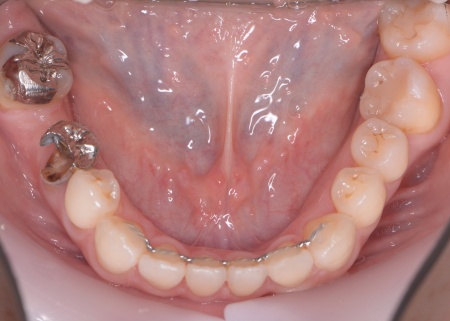

40代女性 矯正治療で噛み合わせを整えたあとセラミックの被せ物・詰め物で修復した症例

また、噛み合わせを確認したところ、奥歯で噛み合わせた際に上下の前歯が当たらず隙間ができる開咬(かいこう)が認められました。

開咬は前歯で食べ物を噛み切りにくくなるだけでなく、噛む力のバランスが崩れて奥歯に負担が集中しやすくなります。

実際に患者様の場合も、特定の歯に長期間強い力がかかり続けたことで歯や修復物の破損、さらには口腔内全体のトラブルにつながった可能性が高いと考えられました。

まずは矯正治療を優先し、噛み合わせが整ってから虫歯の再発リスクの低いセラミックの被せ物・詰め物などで歯の形態と機能を回復する方針を提案し、同意いただきました。

矯正治療終了後、改めてお口の中を確認したうえで、歯の状態に合わせ虫歯の除去や土台の修復を丁寧に行い、精密な型取りを実施しています。